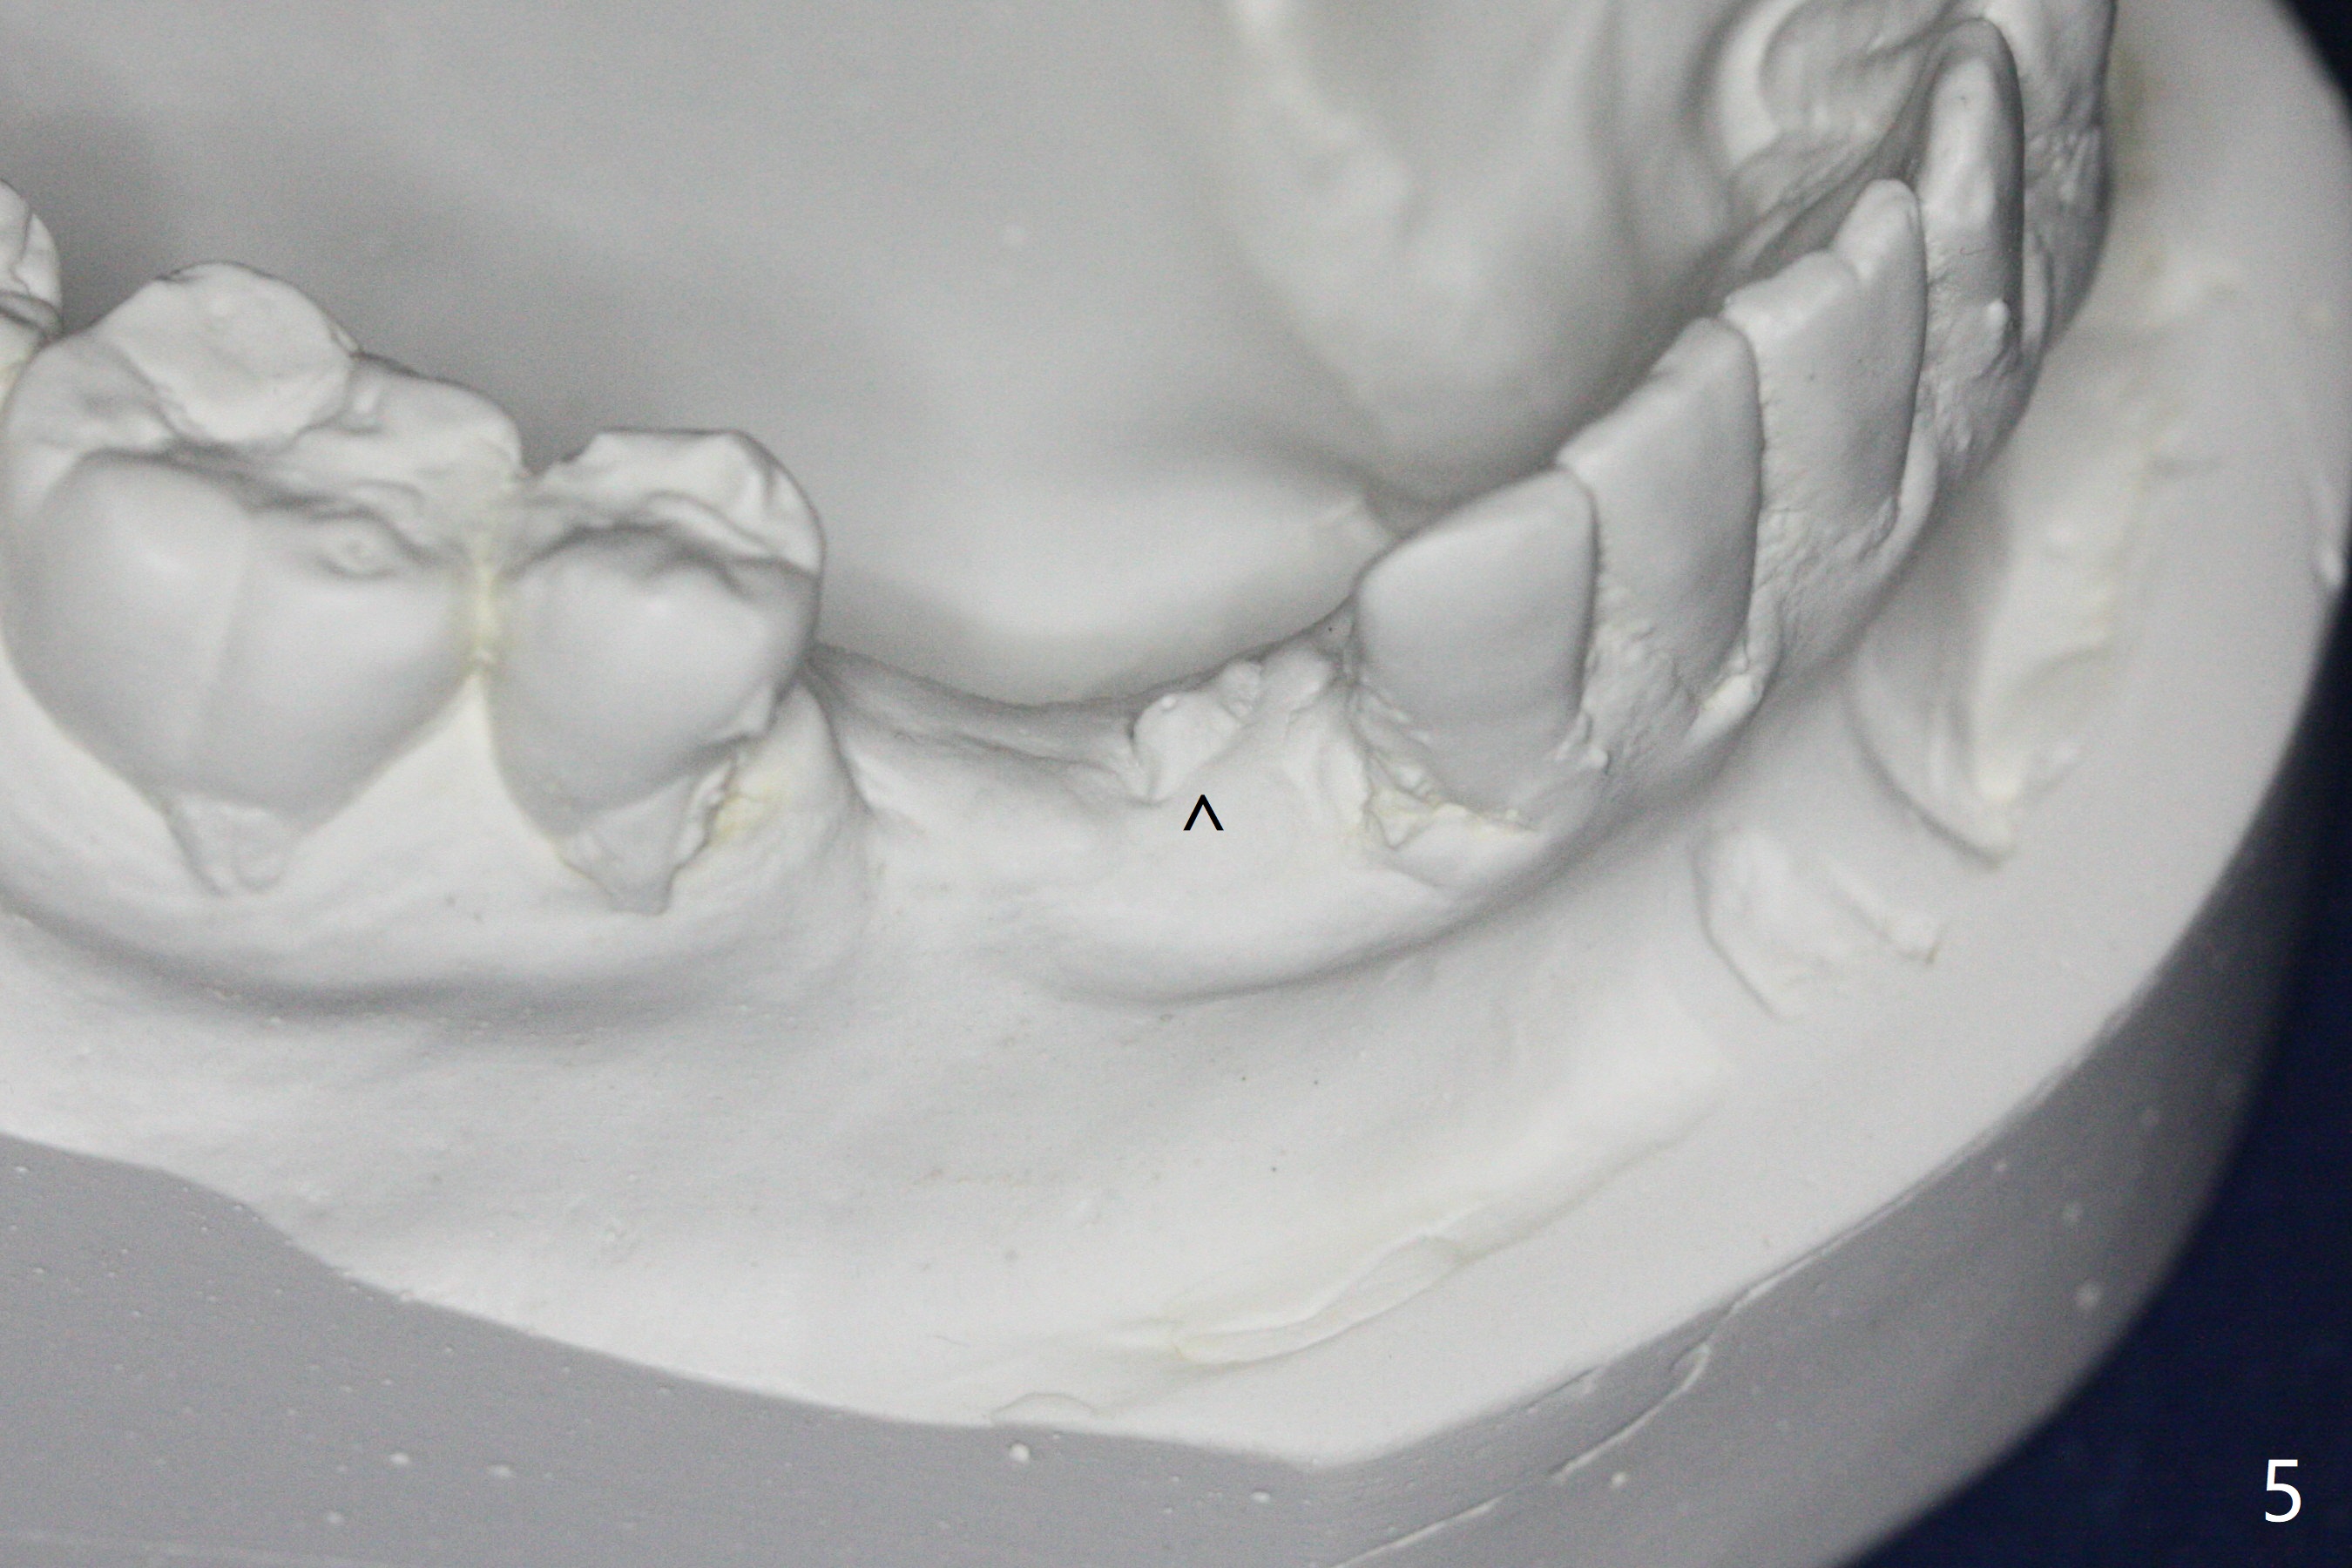

When the surgical guide for #28 is removed, the 4x13 mm implant is found to be superficial and buccal. Part of the buccal mucosa is nonkeratinized. After 1 mm deeper placement of the implant, CT confirms the buccal placement (Fig.1, as compared to design). In fact the guide was doubly checked for fitness prior to osteotomy, but grossly it seemed to be seated properly. The suspicion is related to the trimming at the site of #27 (Fig.2,3 (*), as compared to a mounted model in Fig.4,5 (arrowhead) and the model sent to lab for guide fabrication). The lab agrees to redesign the case. There is a narrow buccal band 1 week postop (Fig.6). The patient is a smoker. The implant was placed buccal (Fig.7, 1 month postop). A new 4x13 mm implant is placed on the top of the 1st line following 3x14.5 mm drill (Fig.8 (35 Ncm)). In fact the implant position is not changed much. Four months post banding (20 ss) and 2 months post 2nd implant placement, the tooth #27 is exposed for bracket; extrusion is initiated (Fig.9). In 3 weeks of retraction, the bracket is supragingival (Fig.10). The canine contacts the distal healing abutment with 2 months of retraction (Fig.11). It seems necessary to initiate lower bracket placement. There is no bone loss 4 months postop (Fig.12). A 4.5x7(4) mm abutment is placed (Fig.13) for a temporary crown as an anchor (Fig.14) to further extrude #27 with continuous inter-arch retraction (to reduce tension upon #26 with severe bone loss (Fig.12)). LR3 extrusion is incomplete, although there is an increase in bone distal to LR2 ~ 10 months of extrusion (Fig.15).